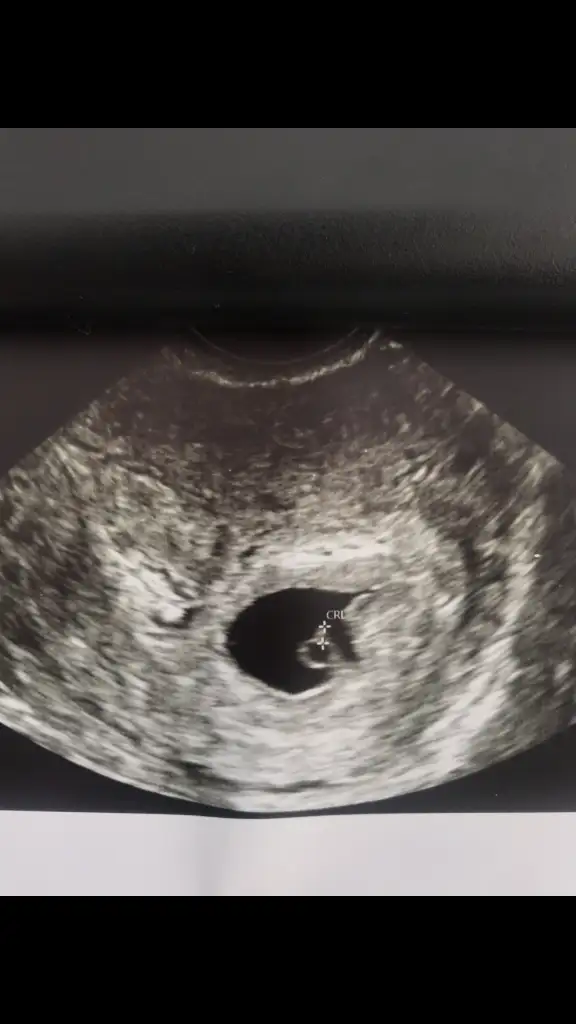

8 haftalik vajinadan bakıldı sağda bonadeas

• IMG_20210215_192449.webp

18,7 KB · Görüntüleme: 98

• IMG_20210311_170803.webp

51,5 KB · Görüntüleme: 94

ılk fotoda 6 haftalık vajınal oldugu gbi cektım

2. de de 8 haftalık yine vajinal